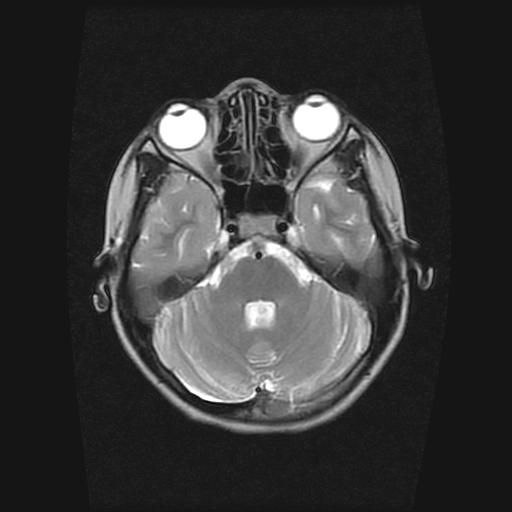

9岁女孩,三岁时诊断为癫痫,一直服丙戊酸钠,现患者一般情况良好,家长复查核磁片,看能否停药..

巨脑回

未见异常信号灶.

未发现异常信号。